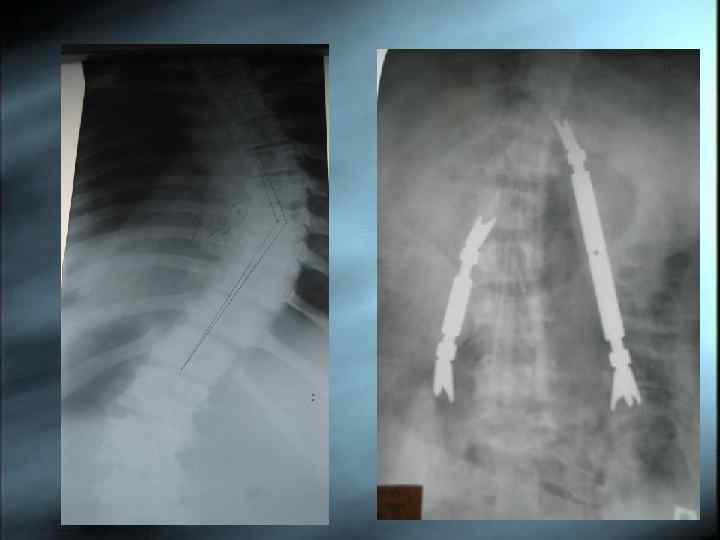

Оперативное лечение Оперативное лечение